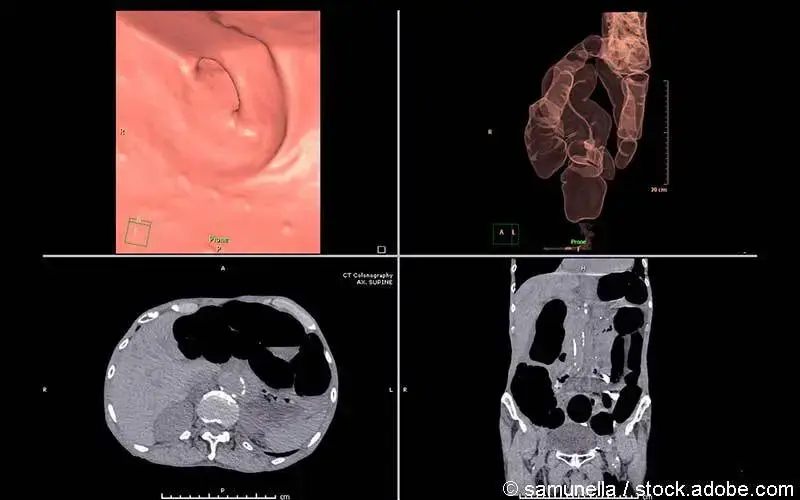

Computertomographie

Eine CT-Untersuchung wird bei Verdacht auf Metastasen in Lunge oder Leber eingesetzt. Mitunter kommt auch eine CT-Kolongraphie zum Einsatz. Mit dieser virtuellen Koloskopie wird das Kolon in 2-D und 3-D-Bildern sichtbar. Nachteil ist jedoch die fehlende Möglichkeit zur Biopsie.